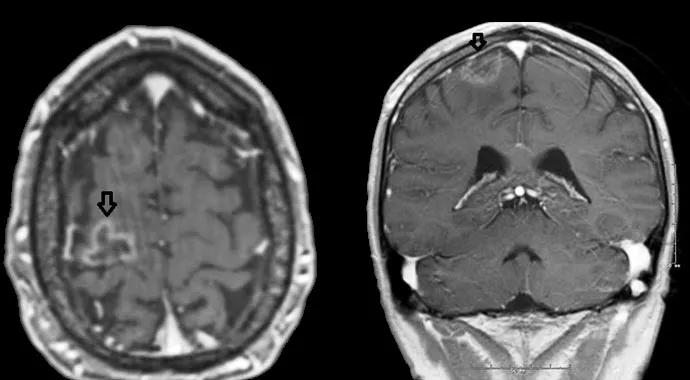

For now, however, the case patient remains fully functional and is able to live independently and work. The figure below presents axial and coronal images showing the size of his lesion at a recent follow-up appointment. Each time he looks at his providers with his gentle, smiling eyes and shakes our hands with his own hand calloused from hard work as a carpenter, there is no doubt about the huge impact on his life made by this pioneering treatment approach and all the care received from his multidisciplinary management team.

Figure. Axial and coronal brain images of the patient at a recent follow-up visit. Arrows point to his lesion.